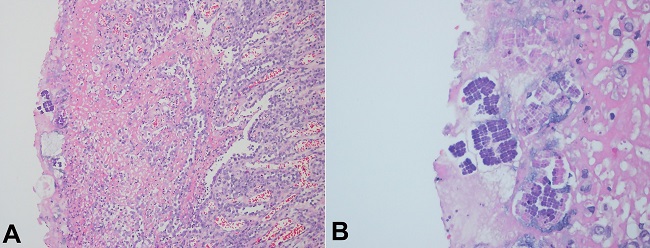

Patient’s body was sent to autopsy after the family authorization. Macroscopically there was a 6cm perforation at the transition of the body and antrum of the stomach, and the gastric mucosa was congested and hemorrhagic. Microscopic revealed ischemic necrosis of the stomach wall, polymorphonuclear cells in the lamina propria and inside vessels of mucosa and submucosa, and bacterial colonies close to the perforation site, formed by basophilic cells, arranged in cuboids, tetrahedral structures, compatible with the diagnosis of Sarcina ventriculi (Figure 1A and 1B).

A 58-year-old male patient, a former smoker, was submitted to an upper gastrointestinal endoscopy due to epigastric pain in the past three months. Hemoglobin level was 10.8g/dL (reference range 12.8-17.8g/dL), and no other laboratory abnormality was detected. The upper gastrointestinal endoscopy demonstrated a non-obstructive neoplastic lesion in the antrum of the stomach, confirmed by biopsy as a diffuse gastric adenocarcinoma with signet-ring cells. CT scan revealed no distant metastasis, and patient was submitted to a partial gastrectomy. Anatomopathological analysis of the specimen confirmed a poorly differentiated adenocarcinoma, with 5.5cm at the distal stomach and extending through all gastric walls. There were free resection margins and no metastasis was seen in any of the seventeen lymph nodes (pT3 pN0). Sarcina ventriculi was identified at the mucosa (Figure 2A and 2B). The patient had a good recovery after the surgery, but was readmitted due to a wound infection, treated with local drainage and antibiotic therapy. He is currently receiving postoperative chemoradiotherapy (MacDonald regimen).